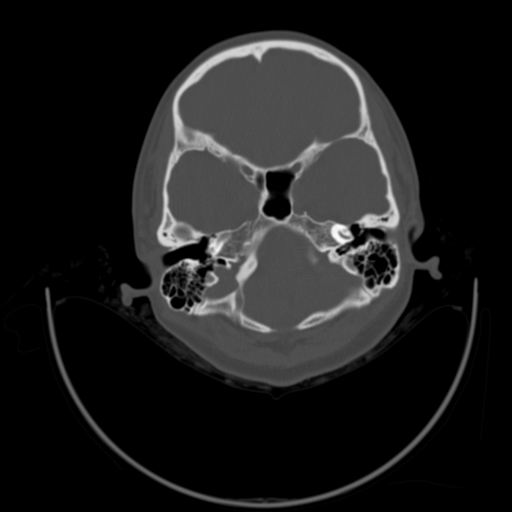

以下是引用随光逐影在2009-3-14 7:58:00的发言:[br]双耳——颞骨ct轴位平扫未见明确异常。